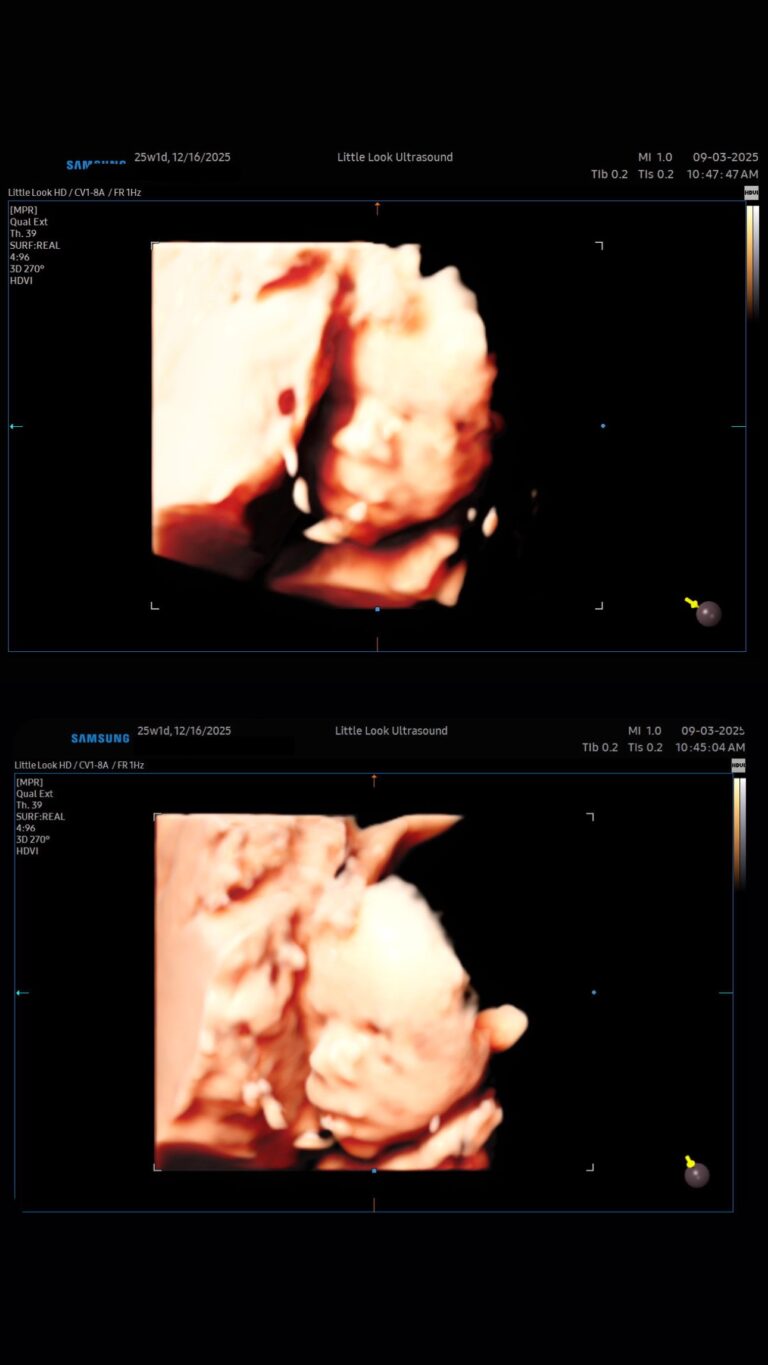

What Do Babies Look Like in the Womb? A Guide to Every Stage of Pregnancy NH MAExpectant parents in New Hampshire and Massachusetts often wonder what their little one looks like before birth. Thanks to the advancements in 3D ultrasounds, families can now see their baby’s development more clearly than ever. From those first tiny features to the moment they’re ready to enter the world, here’s a look at what your baby looks like…

Why 3D Elective Ultrasounds Make the Perfect Pregnancy Keepsake in Southern NH & Northern MAPregnancy is a once-in-a-lifetime experience, and every moment feels worth remembering. While traditional ultrasounds are special, 3D elective ultrasounds in southern NH offer a whole new way to bond with your baby — and create keepsakes you’ll cherish for years. A Window Into Your Baby’s WorldUnlike flat, black-and-white 2D scans, 3D ultrasounds provide lifelike images…

The Best Time for a 3D 4D UltrasoundIf you’re planning a 3D ultrasound in Londonderry, NH, timing is everything. Choosing the right stage of pregnancy can mean the difference between faint outlines and breathtaking images of your baby’s tiny face. When to BookThe ideal time for a 3D ultrasound is typically between 27 and 32 weeks. By this stage, your baby has…